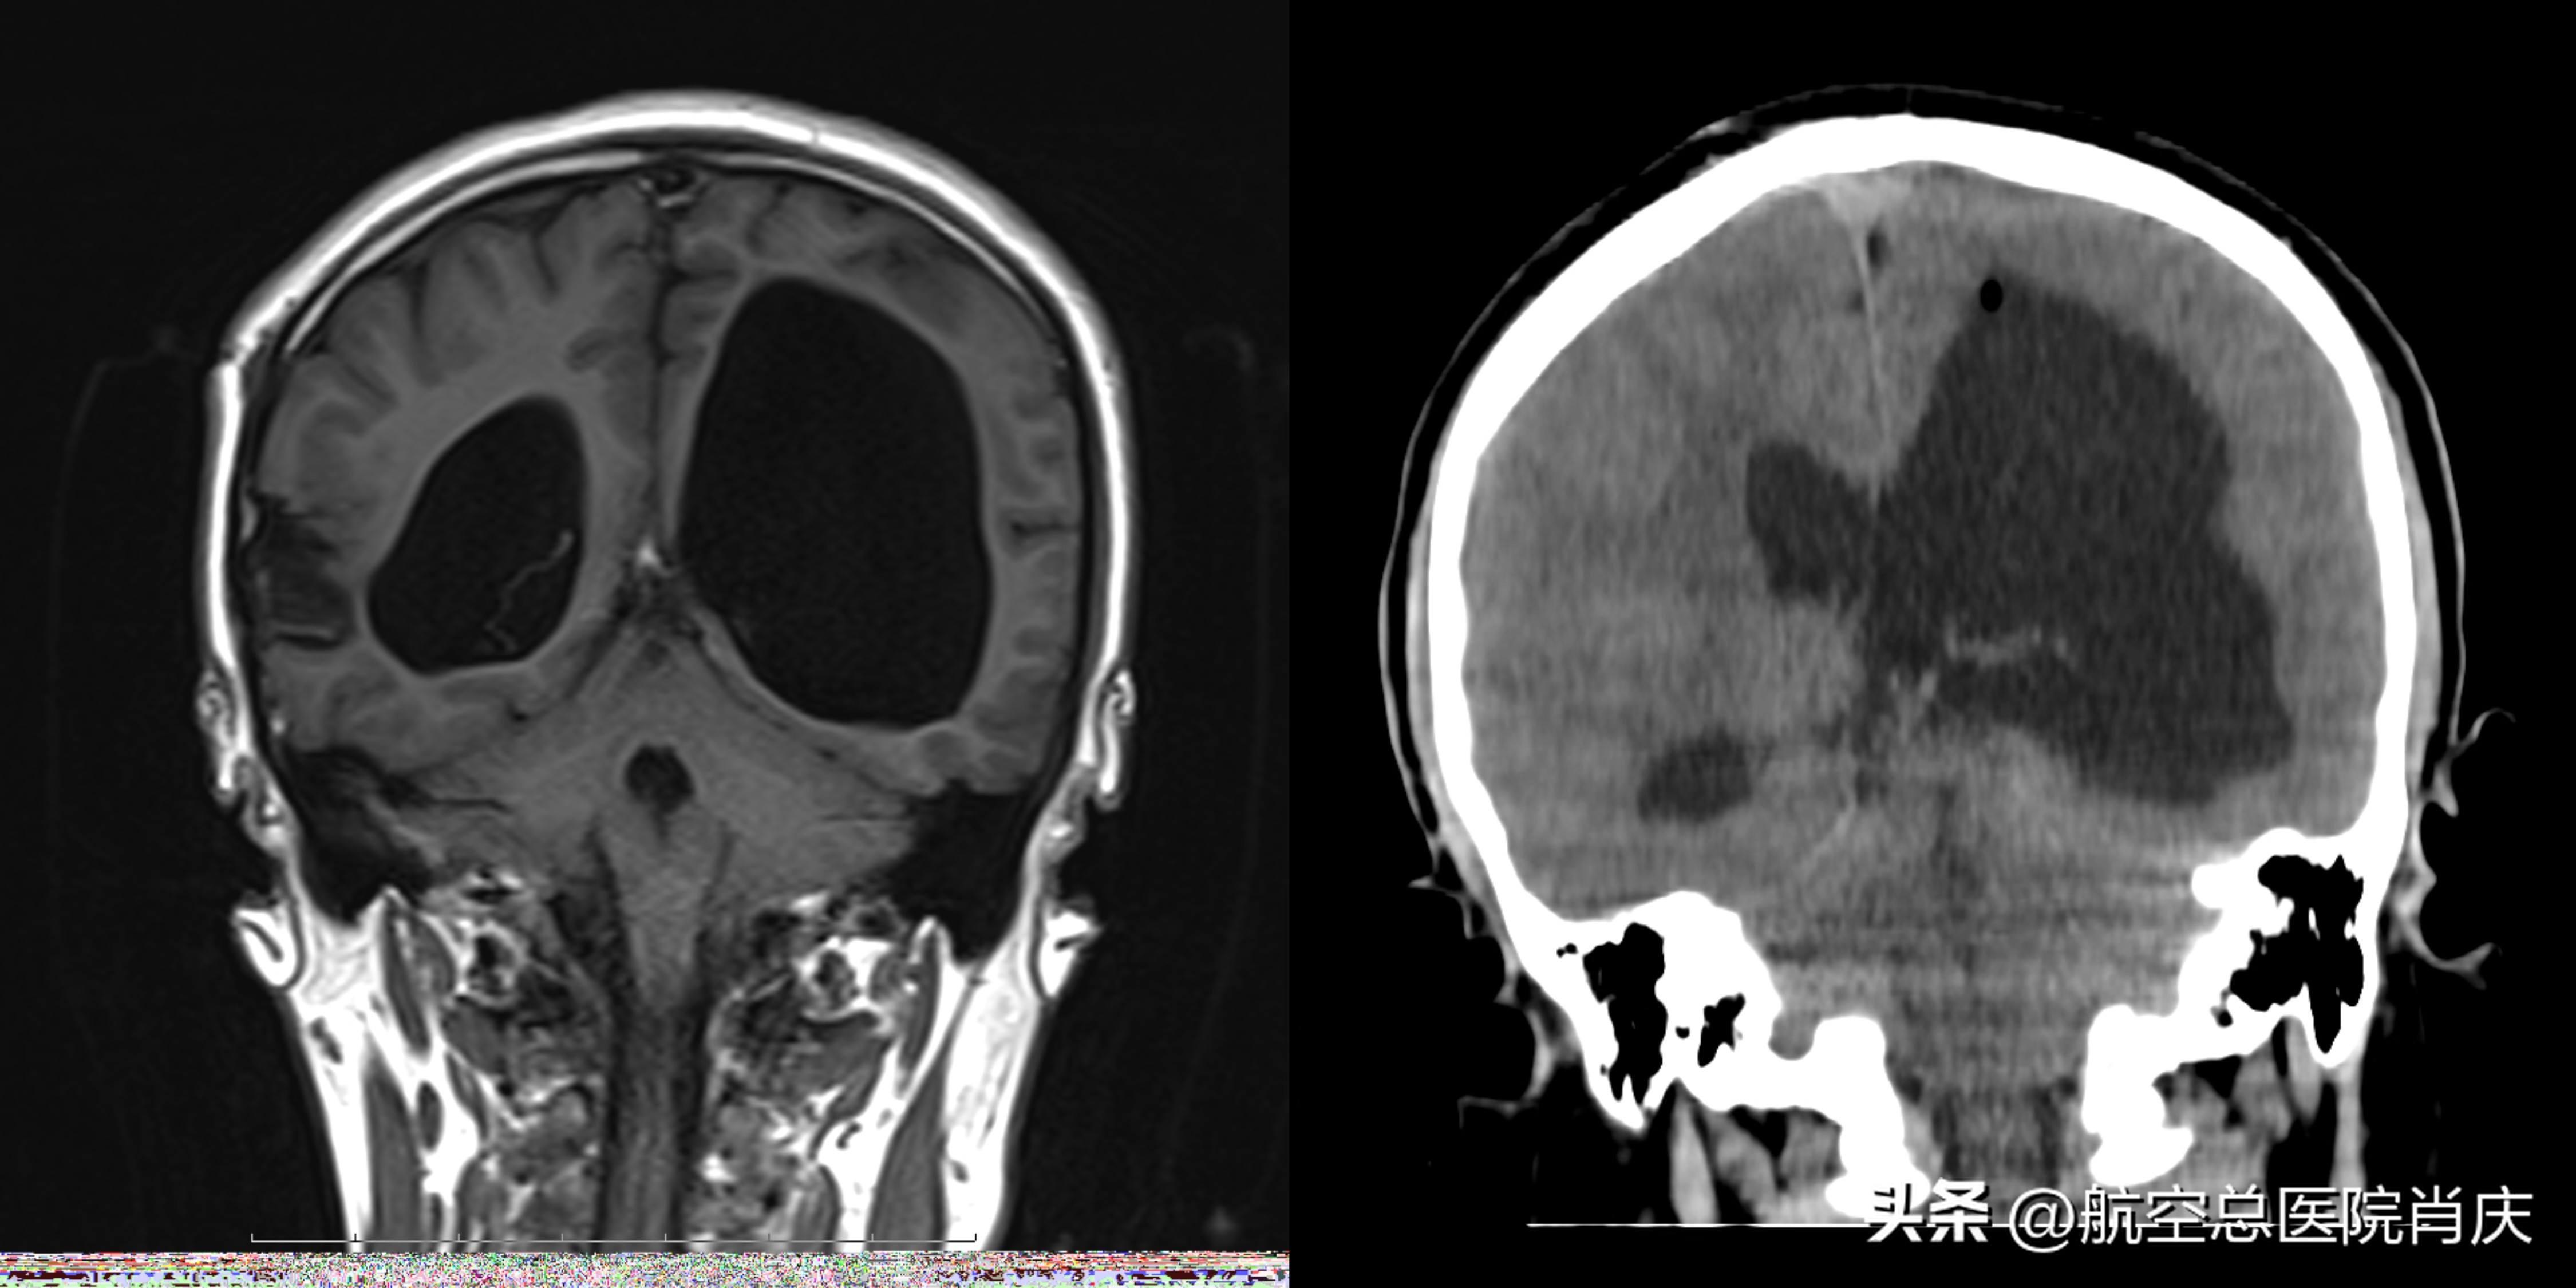

术前术后对比冠状位

神经内科住院部请肖庆主任会诊,给出诊疗方案。根据患者影像学检查左侧脑室扩张,室间孔闭塞可能,导水管可疑梗阻,但不除外脑脊液吸收张障碍。患者目前脑积水解剖定位病变于扩张脑室,根据患者病情,脑积水需手术治疗。方案1、手术可选择脑室腹腔分流术治疗,脑室腹腔分流术可存在术后感染、梗阻。方案2、脑室镜下脑室探查术可明确脑室内情况,酌情行导水管扩张、透明隔造瘘、三脑室底造瘘术,支架植入中脑导水管造瘘术治疗,重建脑脊液内循环,借助基底动脉搏动进一步改变脑脊液循环动力。向家属说明治疗方案后,患者及家属不想身体里一直有一根管子存在,时时提防着各种并发症,希望肖庆主任对患者进行内镜检查治疗。